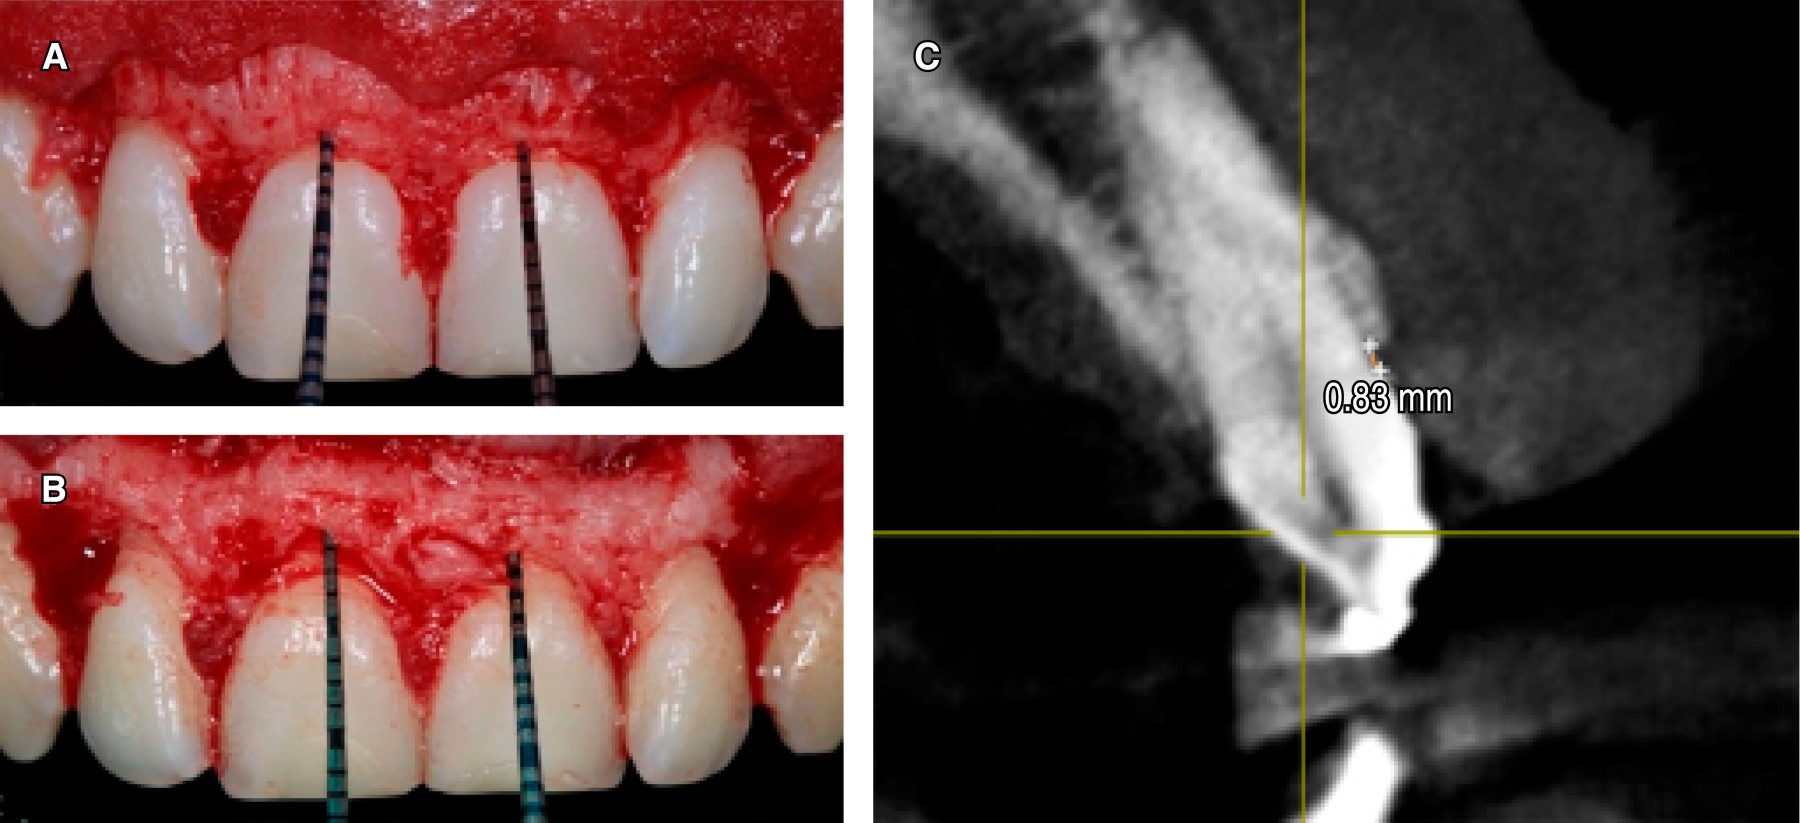

Se procede a medir las coronas clínicas del 1.3, 1.2, 1.1, 2.1, 2.2, 2.3 (nomenclatura FDI) con una sonda periodontal milimetrada [UNC-15 Hu-Friedy: 1 mm cada raya] (Figura 2), se toma la medida desde el margen gingival al borde incisal de cada órgano dental, se colocan varios puntos de resina fluida en cada pieza dental a nivel de la mitad de la corona clínica, con el fin de poder medir con precisión la curvatura convexa de la corona dental en la tomografía 3D [Orthophos XG 3d ready ceph/ Sirona] (Figura 3). Se procede a toma de la tomografía y posteriormente se realizan los trazos de las líneas para poder medir el tamaño real de la corona anatómica.

Se midieron las coronas clínicas en milímetros de cada pieza dental utilizando la técnica tradicional con sonda periodontal como se refleja en la Tabla 1.

En el examen radiográfico tridimensional se procede a dividir la corona del diente en dos partes trazando dos líneas: Línea A (se mide en mm del tope de resina fluida al borde incisal [BI] del diente) y una Línea B (se mide en mm desde el UCE al tope de resina fluida), se suma la línea A más la línea B para dar como resultado la longitud de la corona dental (Figura 6) (Tabla 2).

Se tomó la decisión de realizar la osteotomía y osteoplastia con el objetivo de dar el espacio al tejido supracrestal o espacio biológico (Tabla 5) (Figura 7 A y B) y así permitir una inserción del tejido conectivo y epitelio de unión; se tomó la referencia de Gargiulo y colaboradores donde el espacio biológico está formado por 0.97 mm de epitelio de unión y 1.07 mm de tejido conectivo, sumando 2.04 mm.14